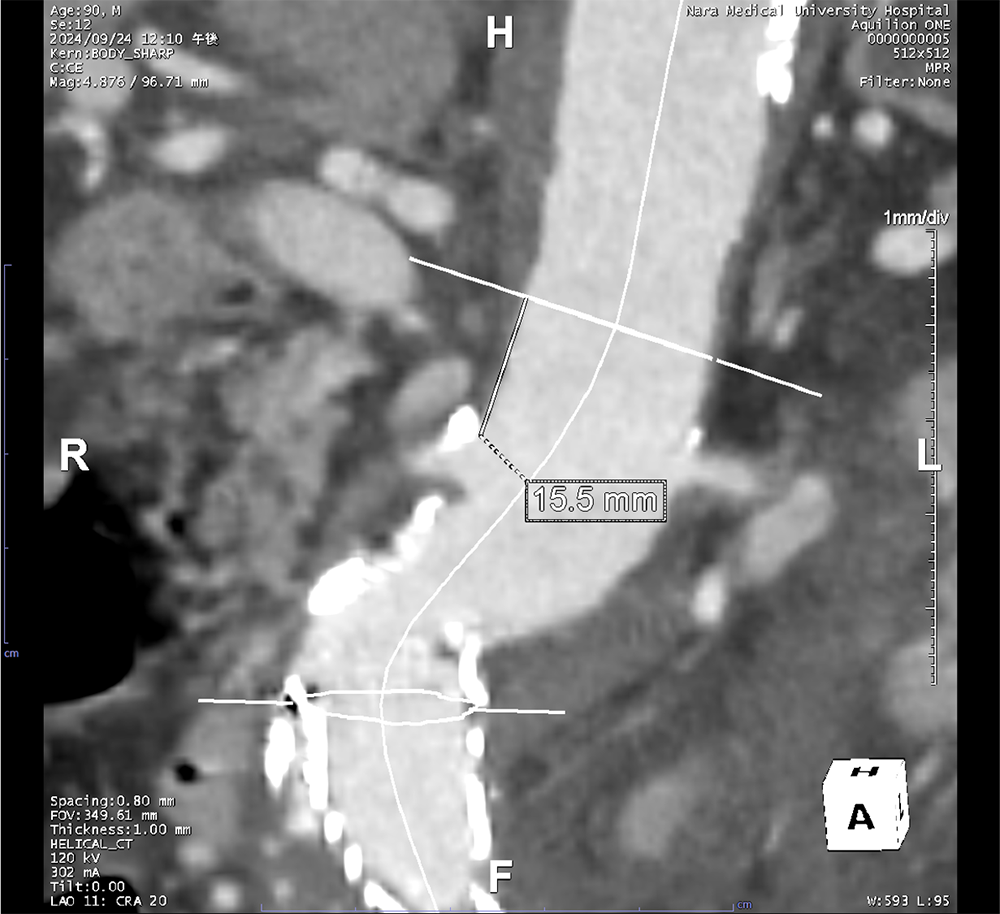

EVAR後の腹部大動脈瘤破裂に対し追加EVARを施行した一例

当科で腹部大動脈瘤に対しEVAR術後、瘤増大傾向で外来フォローアップされていた。急激な腹痛で来院し造影CTが撮影された。瘤内にType1aエンドリークを認めるほか、瘤内解離、破裂を認めた。緊急で追加EVARが行われ、治療後エンドリークは消失し、術後経過も問題なく退院となった。

腹部大動脈瘤(AAA)の診断と治療戦略の決定において、造影CTは最も信頼性の高い検査である。造影CTにより瘤の存在部位や最大径、長さ、形状を正確に評価でき、拡大速度や形態の異常といった破裂リスクの判定にも用いられる。また、瘤壁の不整、壁在血栓、壁内血腫の有無を描出することで、切迫破裂や破裂の診断に直結する。さらに、腎動脈・内腸骨動脈・下腸間膜動脈など主要分枝との位置関係を明らかにすることで、開腹術かEVARかといった治療適応の判断やステントグラフトのデザイン決定に不可欠である。未破裂AAAの経過観察にもCTが推奨されており、腹部超音波に比べ測定誤差が少ない一方、腎機能障害などの可能性を考慮する必要がある。破裂または切迫破裂が疑われる場合には、後腹膜血腫や造影剤漏出を迅速に描出し、緊急治療の判断に直結するため、診断と治療計画の双方において中心的役割を担う。